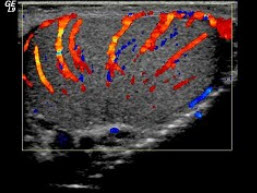

9、单项选择题

患者,男性,甲状腺一侧可触及包块,超声见边界清晰的低回声光团,包膜完整。如图所示,最可能的诊断为()